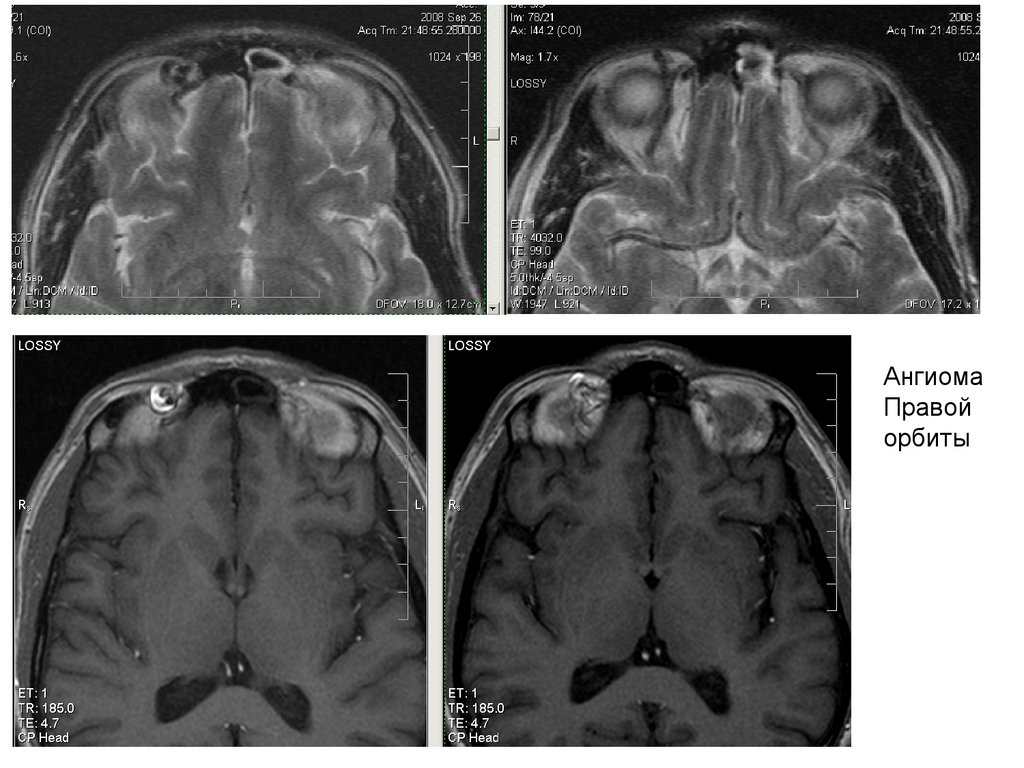

Ангиома

Правой

орбиты